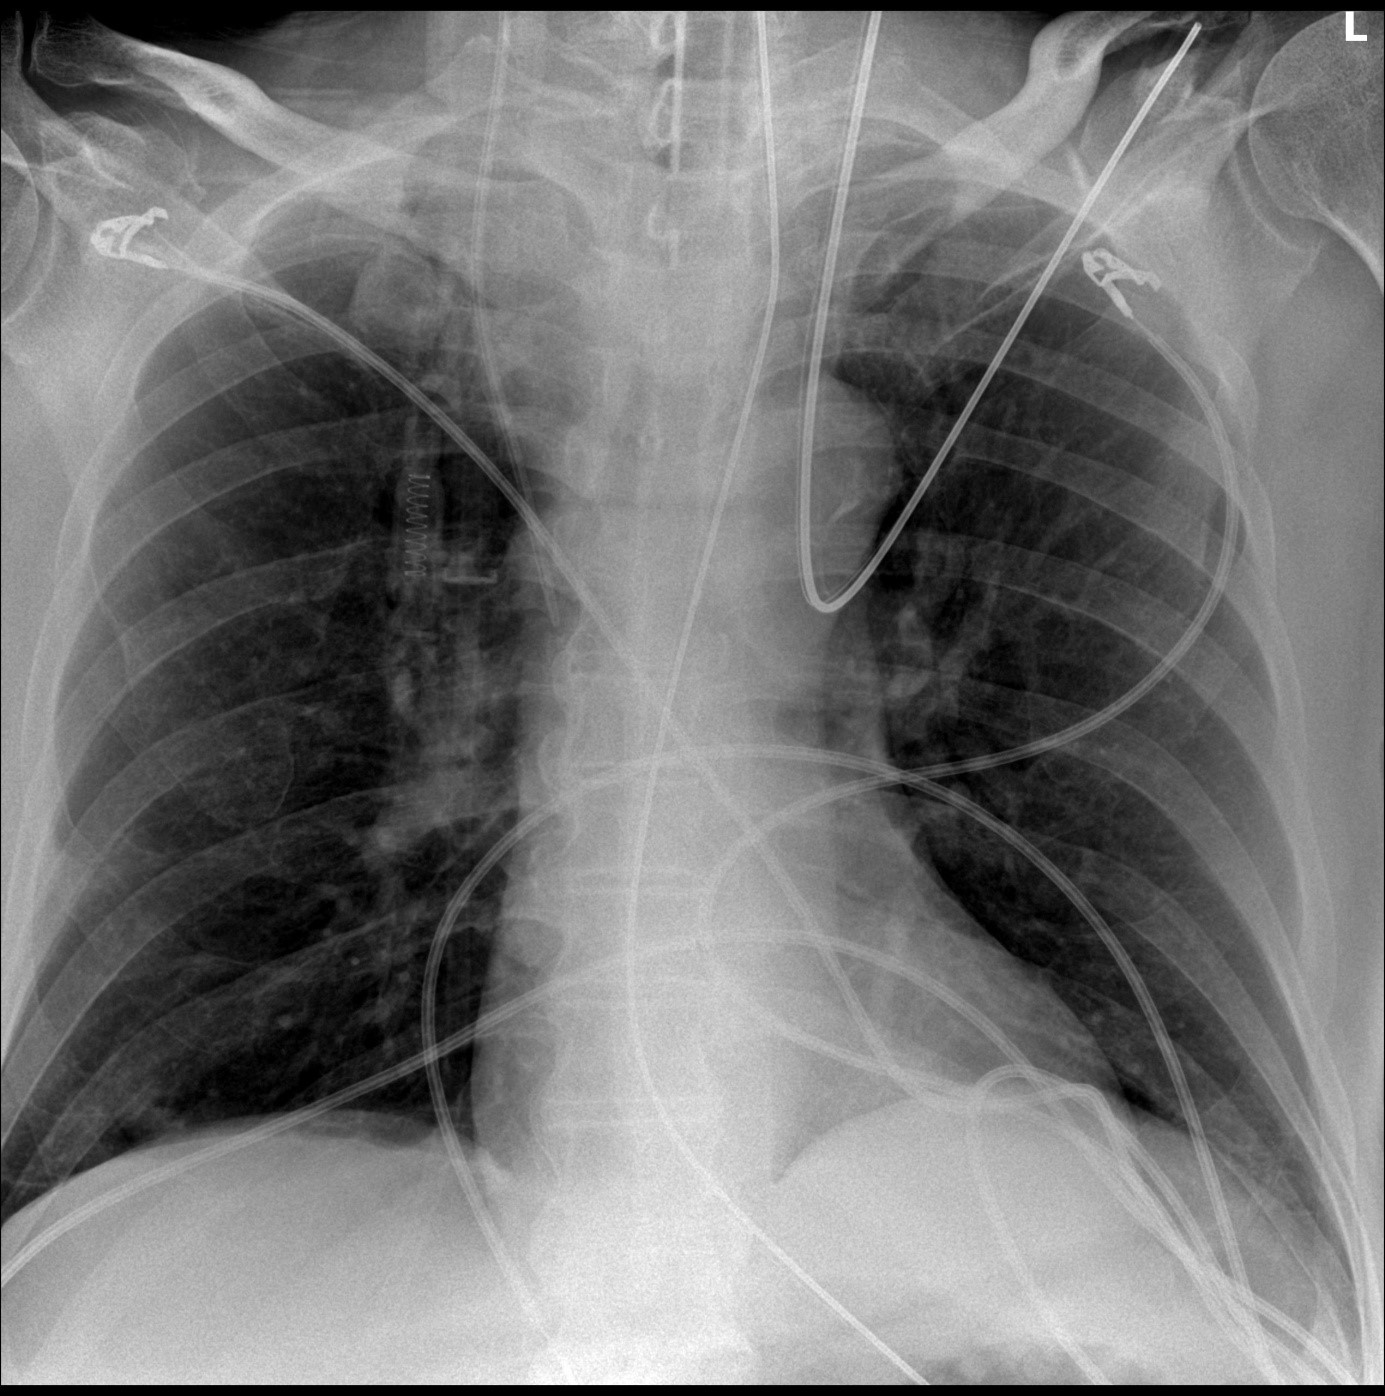

Laboratory investigations revealed a white blood cell count of 9.8 × 10^9/L with normal differential, hemoglobin 13.6 g/dL, platelet count 245 × 10^9/L, and normal renal and liver function tests. Chest radiography performed in the emergency department after intubation showed no obvious infiltrates, masses, or pleural effusions (Fig. 1).

Figure 1. Chest radiography of a 71-year-old man presenting with refractory bronchospasm to the emergency department.